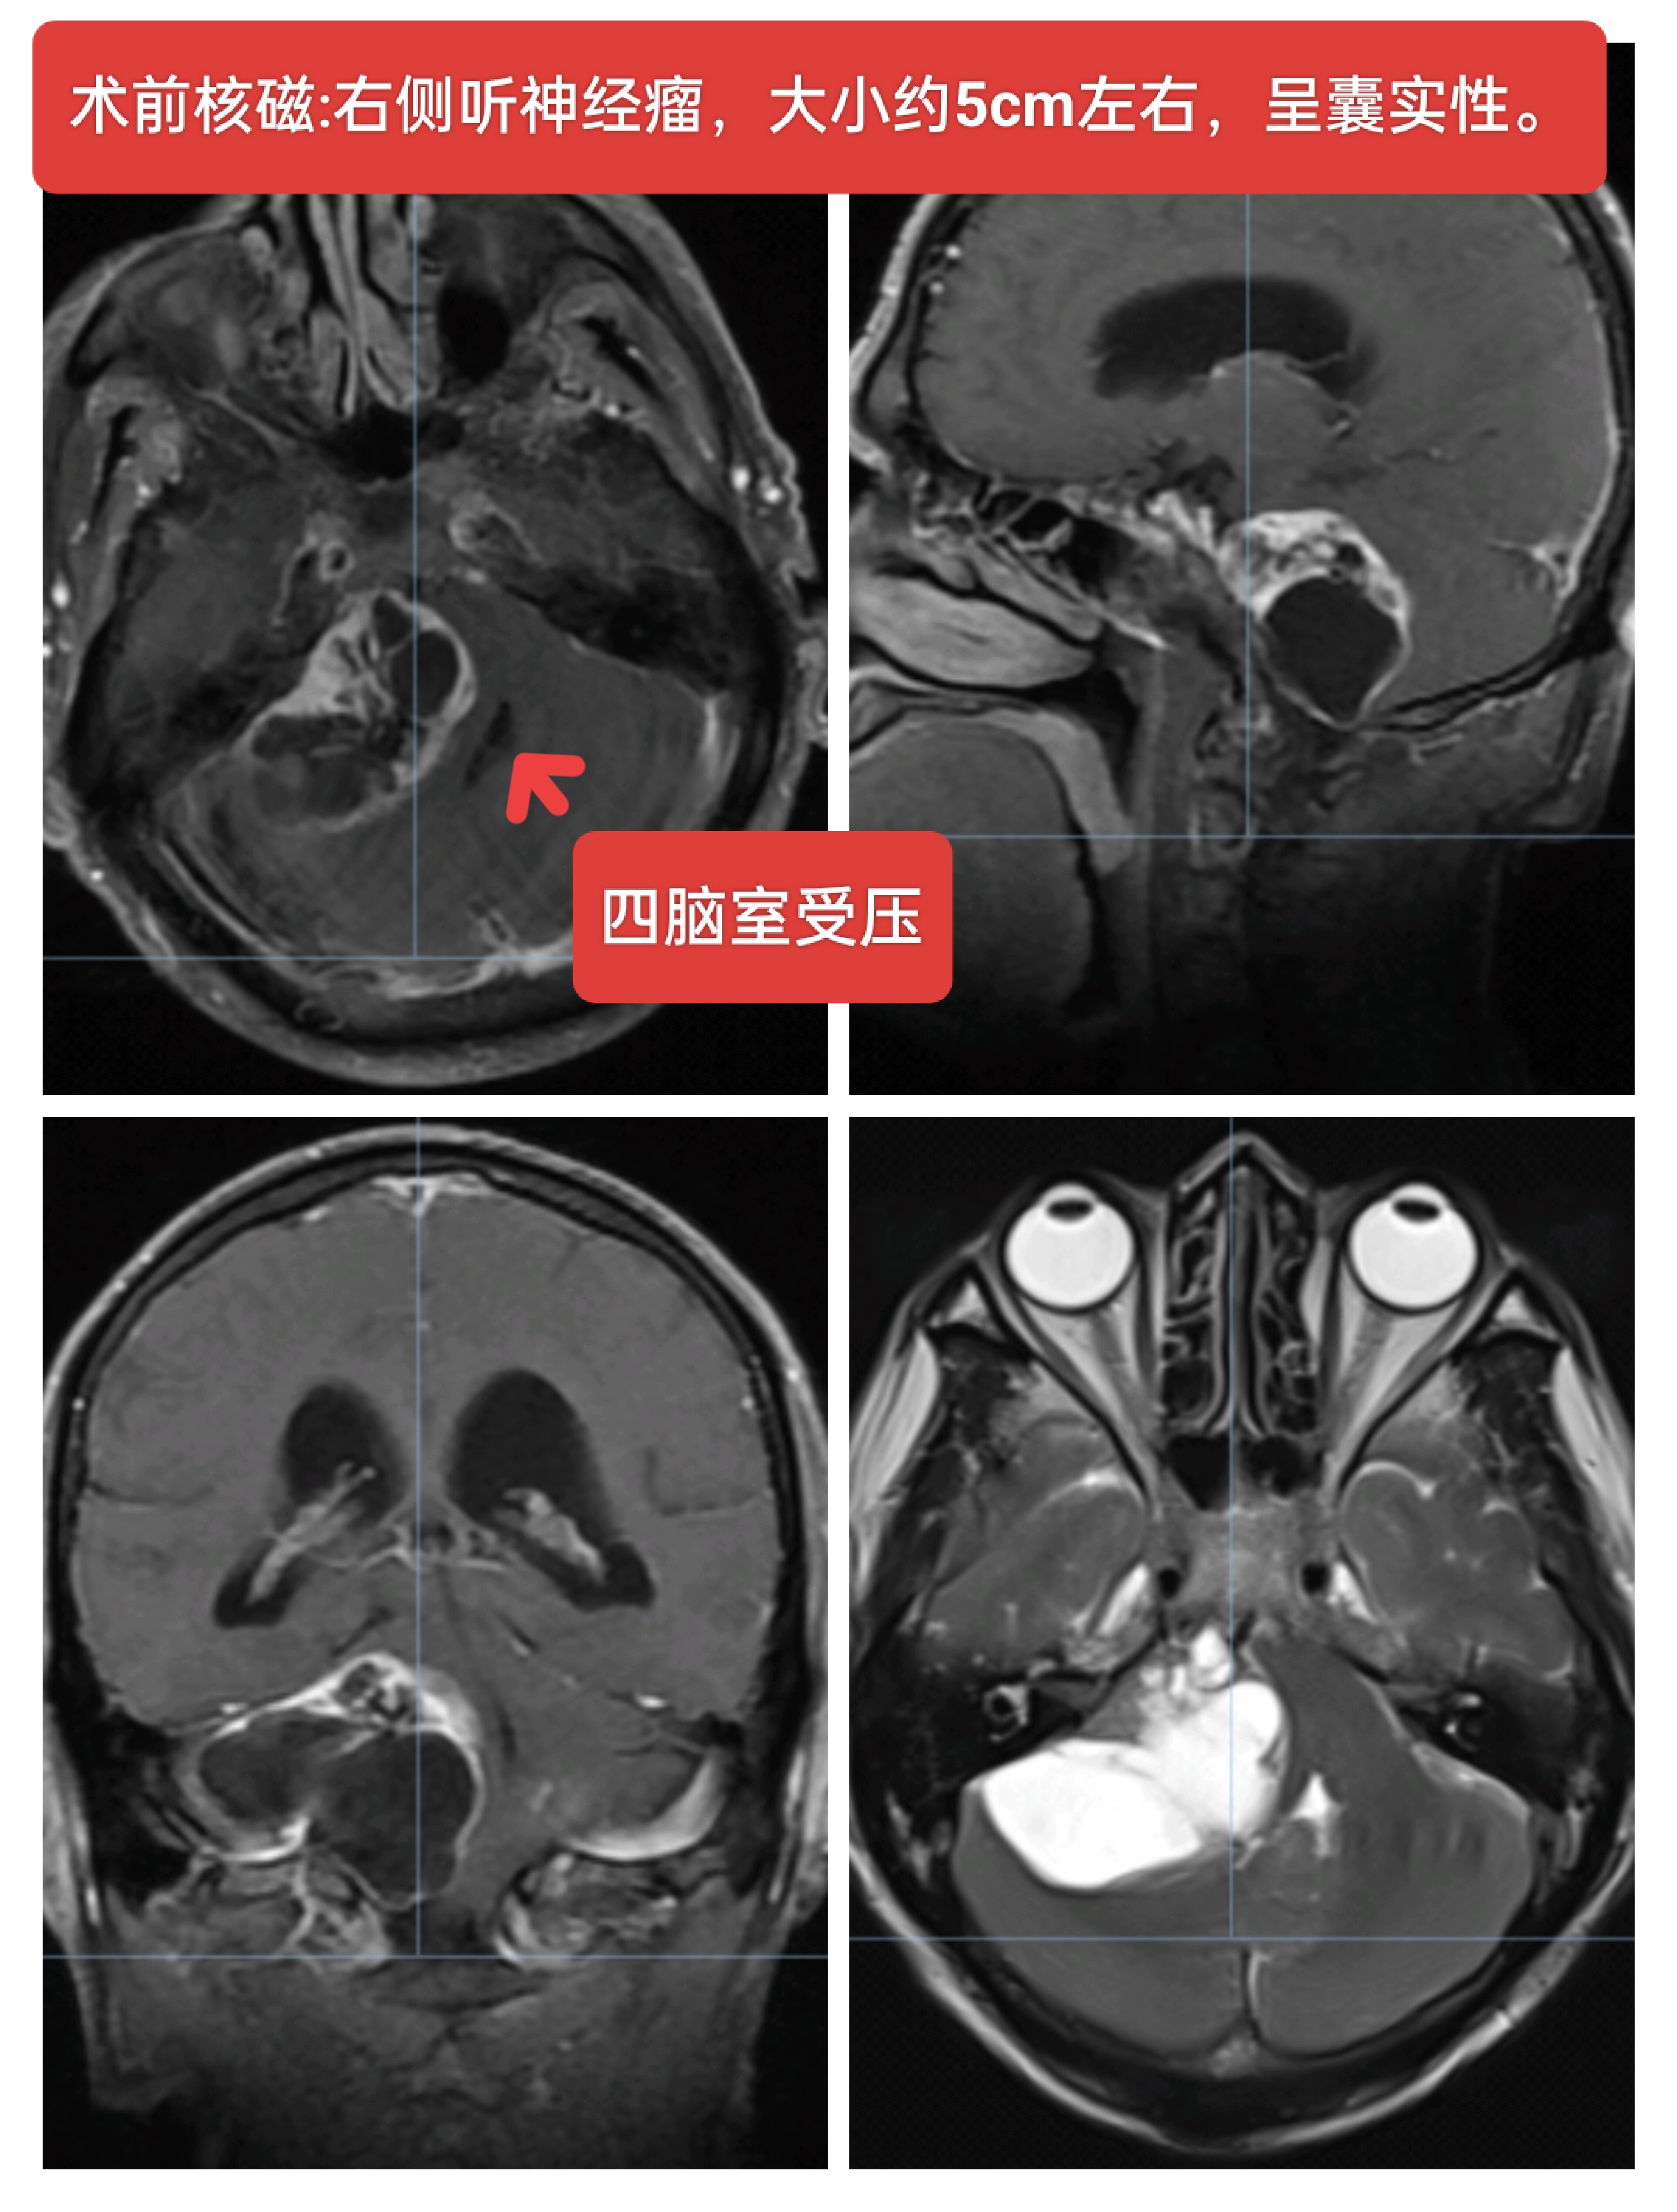

右侧听神经瘤,男性64岁,听力下降一年主诉入院,核磁检查提示右侧CPA区囊实性占位,大小约5cm左右,常规行神经电生理监测下肿瘤切除术,术中面神经保留,术后轻度面瘫。